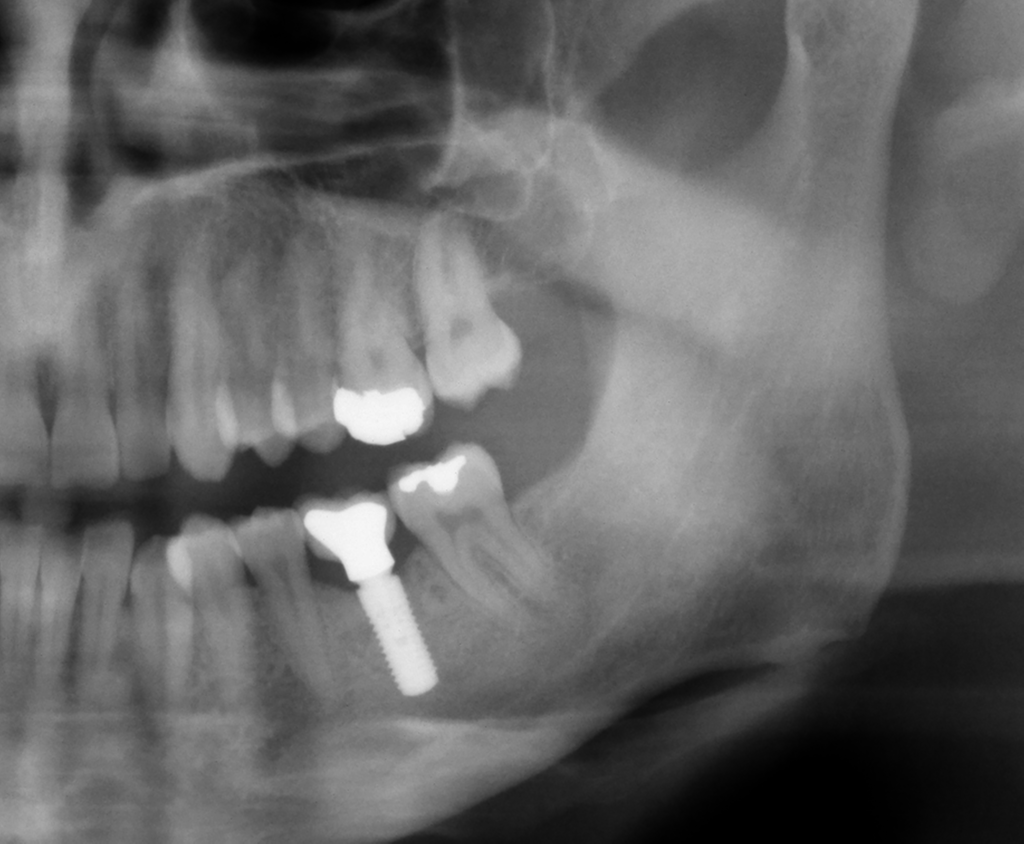

Neben der Frage nach der Chance des Zahnerhalts stellen Patienten häufig die Frage, ob sie durch die WSR Nachteile zu erwarten hätten, wenn sie sich später, bei Fehlschlag der WSR für ein Implantat entscheiden würden (Abbildung 6).

Bei 11,5 Prozent des Gesamtkollektivs (94 Fälle) war eine Wurzelspitzenresektion durchgeführt worden. In 19,1 Prozent der Fälle der Gruppe A (mit vorangegangener WSR) und 26,6 Prozent der Fälle der Gruppe B (ohne WSR) wurde im Rahmen der anschließenden Implantattherapie eine hartgewebliche Augmentation durchgeführt: Der Unterschied war nicht signifikant (p = 0,12). Auch bei der der Fünf-Jahres-Implantatüberlebensrate (Gruppe A: 96,6 Prozent; Gruppe B: 98,0 Prozent) und dem marginalen periimplantären Knochenverlust wurden während des Fünf-Jahres-Follow-ups zu keinem Zeitpunkt signifikante Unterschiede zwischen beiden Gruppen berechnet [Kreisler et al., 2022].

Die Daten zeigen, dass eine vorangehende WSR die mögliche spätere Implantattherapie nicht negativ beeinflusst. Dies trifft sowohl für den Behandlungsaufwand als auch für die Implantatprognose zu. Es ist aus unserer Sicht wichtig, dies in jedem Aufklärungsgespräch auch so zu kommunizieren.